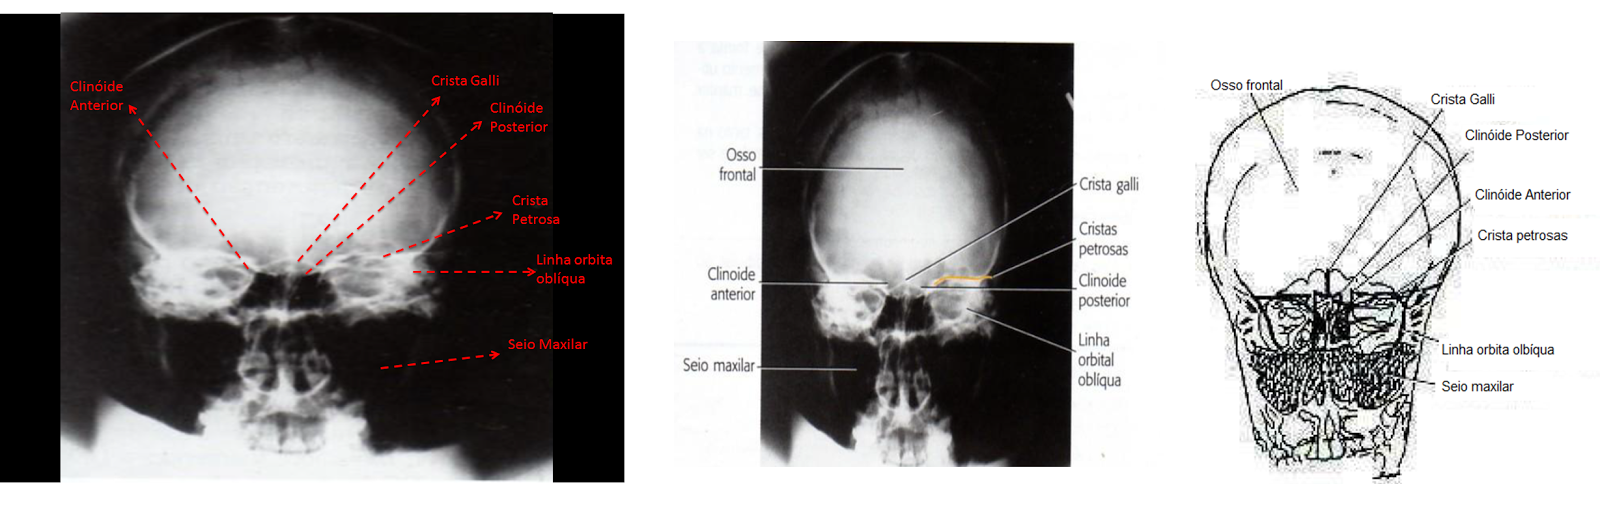

Critérios de visualização: Osso frontal, crista galli, condutor auditivos internos, seios frontais e células etmoidais anteriores, cristas petrosas, asas maiores e menores do esfenóide e dorso da sela.

Posição: A ausência de rotação é evidente, como indicado pelas distancias iguais bilateralmente da linha orbital oblíqua até a margem lateral do crânio. Cristas petrosas preenchem as órbitas e se sobrepõe à região orbital superior.

Clinóides posteriores e anteriores são visualizados logo acima das células etmoidais.